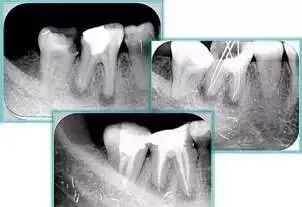

( 2 )X片共四张 (术前、诊断丝 、主牙胶尖确认、术后)。

共有 4 张 X 线片,分别是术前、诊断丝 、主牙胶尖确认、术后。

( 1 )术前:术前 X 线片用来了解牙齿的大概情况。术前预期为多根牙时 X 线片应偏头拍摄。

( 2 )诊断丝:根据术前 X 线片进行开髓、根管的初步预备后,需要插入诊断丝,用来指示工作器械位置。常用 10 号或 15 号扩大器作为诊断丝插入牙髓腔。

( 3 )主牙胶尖确认:通过术前预期和诊断丝诊断,明确工作长度、牙根走向,进行根管预备。之后应进行主牙胶尖(中锉)确认,已明确根管是否适合充填。

( 4 )术后:观察治疗效果。